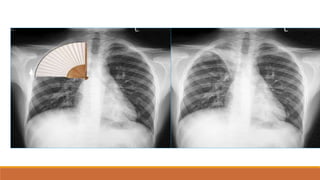

Độ xuyên

thấu tia

-

T

h

ấ

yđ

ược cột sống,

mạch máu sau bóng

tim

Tia yếu (hình

quá trắng)

‐Vòm hoành (T) có thể

không nhìn thấy rõ do

đáy phổi (T) bị mờ 



Giả bệnh lý hoặc ẩn đi

bệnh lý của đáy phổi (T)

‐Các mạch máu phổi có

thể sẽ thấy rõ rang, nổi

bật hơn Nhầm với

suy tim sung huyết, xơ

phổi

Tia cứng (hình

quá đen)